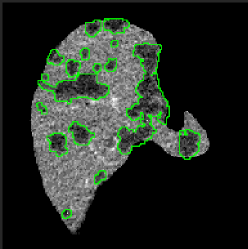

After having the liver segmented, we might directly apply a 3D segmentation network to extract the liver lesions. However, a 3D Network operating only in the liver region is still computationally expensive and may suffer from the problem of lacking 3D training scans. In order to mitigate these issues, we propose to use a mixed network to handle the segmentation of large and small lesions separately. In particular, we use a 2D network to scan slice-by-slice and predict larger tumors if present. However, this method is not sufficient for predicting small lesions, as the false positive examples shown in Fig. 3. This happens due to the appearance of the small lesion matching that of other tissues or vessels on 2D liver slices. A 3D network learning from cropped volumes with small lesions can reduce such false positives, because it leverages the observation that the location of the tissue or vessel appears to travel considerably in-between slices whereas the liver lesion constantly appears to be roughly stationary across slices. Regarding the threshold of the lesion size used to separate the large and small lesions, it may vary for different applications and datasets. Here, we set the threshold as a resolution of by experimentally testing on the LiTS dataset, which greatly balances the prediction accuracy and the computational efficiency.

Large Lesion Segmentation. We use another 2D CompNet like the one used for the liver segmentation (Fig. 2) to extract lesions larger than from the input slices with the liver only. Since this network takes care of the prediction of large lesions, we clean the training masks by using the component labeling [2] to remove all small lesion masks, whose horizontal and vertical dimensions are both less than or equal to 32 on a 2D slice, for every slice. In the test phase we also remove the detected lesions less than using the component labeling.